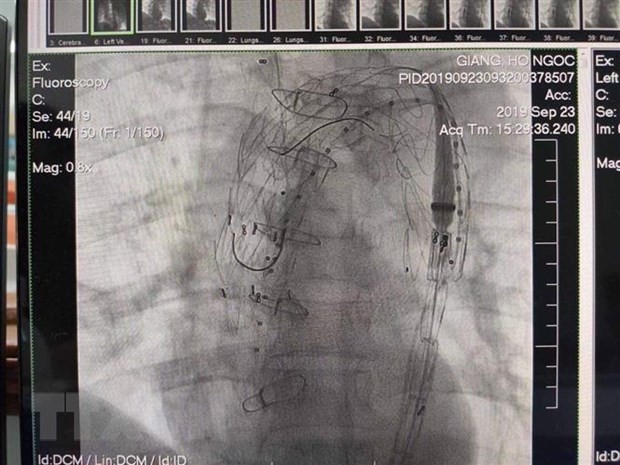

Kết quả can thiệp đặt stent graft động mạch chủ của bệnh nhân. (Ảnh: Mai Trang/TTXVN)

Cụ thể, bệnh nhân Hồ Ngọc G. nhập Bệnh viện Trung ương Huế trong tình trạng đau ngực dữ dội, tụt huyết áp.

Qua thăm khám lâm sàng, các bác sỹ Trung tâm Tim mạch của bệnh viện chẩn đoán đây là trường hợp bóc tách động mạch chủ ngực tuýp B có lối vào nằm sau động mạch dưới đòn bên trái, có tình trạng lan ngược lên các động mạch trên quai động mạch chủ và động mạch chủ lên.

Bệnh nhân được chỉ định mổ cấp cứu thay động mạch chủ lên, chuyển vị các động mạch trên quai động mạch chủ bằng mạch máu nhân tạo và sử dụng phương pháp can thiệp nội mạch để đặt stent graft (giá đỡ bằng kim loại được phủ màng sợi tổng hợp) nhằm điều trị bóc tách động mạch chủ ngực xuống.

Sau 7 ngày phẫu thuật, kết quả kiểm tra cho thấy, tình trạng bóc tách động mạch chủ đã được giải quyết triệt để.